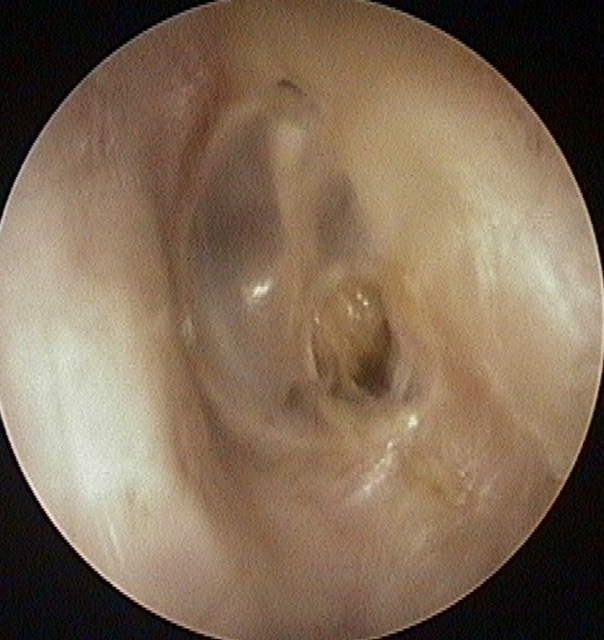

Perforation

Tympanic Membrane